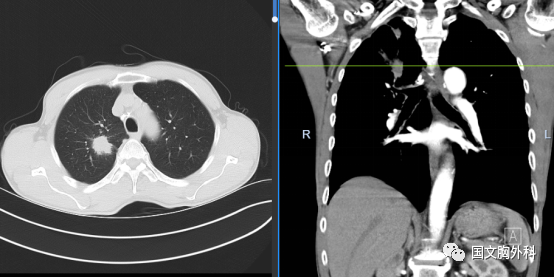

周大爺,發(fā)現(xiàn)肺占位1個月。CT下觀察右肺上葉腫物延續(xù)至肺門,穿刺病理提示:肺鱗癌。有手術(shù)機會,家屬同意手術(shù)治療。

術(shù)中患者右肺門分離困難,決定行右肺上葉袖型切除,在長達(dá)8小時的奮斗后,周大爺手術(shù)順利結(jié)束。